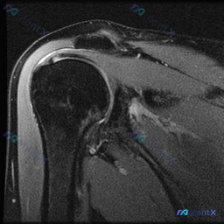

病例影像读片分享 今天整理了一例踝关节MRI的读片资料,把分析思路分享给大家一起讨论。 基本影像信息 这是一张踝关节矢状位T2加权MRI,可以清晰显示胫骨远端、距骨、跟骨、舟骨、楔骨等踝关节复合体骨性结构,T2序列对液体信号显示清晰。 核心阳性发现 1. 多关节广泛积液:胫距关节前后隐窝、距下关节间...

看到一份很有代表性的踝关节MRI影像,整理了资料和分析思路分享给大家。 病例影像基本信息 这是一份踝关节矢状位T2加权像(T2WI),先给大家说下客观观察到的结果: 1. 解剖结构显示清晰:可以看到胫骨远端、距骨、跟骨、足舟骨及部分跖骨 2. 核心异常发现: - 胫距关节腔前方、后方可见明显T2高信...

最近看到这例踝关节MRI读片讨论,问题是「图像中能观察到什么软组织液相关改变」,整理一下完整分析思路,分享给大家。 一、病例影像核心信息 这是踝关节MRI冠状位T2加权图像,核心发现如下: 1. 骨结构改变:胫骨远端、距骨、跟骨显影清晰,距骨穹窿内侧关节面可见局灶性高信号改变,边界清晰,呈楔形凹陷状...